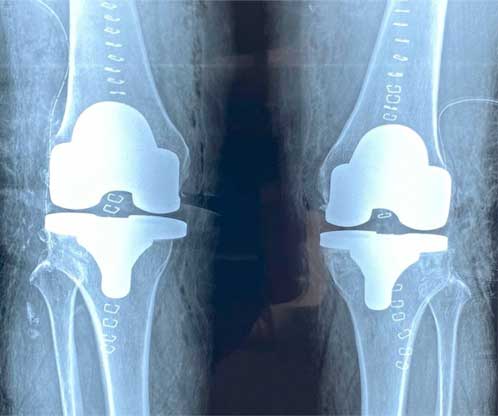

Prótesis de rodilla

También conocida como artroplastia de rodilla, es la sustitución artificial de la articulación desgastada por artrosis con un implante de metal y polietileno que ayuda a aliviar el dolor y restaurar la función.

Cuidados después de la intervención

El paciente puede caminar desde el mismo día de la cirugía, se da de alta a su domicilio a las 24 horas, realiza actividades cotidianas en casa de forma autónoma desde la primera semana, recupera el 80% de la función de la rodilla al primer mes, 90% de la función en el segundo mes y 92% - 98% de la función en el tercer mes.

Resultados esperados

Eliminar el dolor en la zona afectada, mejorar la función como es fuerza muscular, movimiento, estabilidad, biomecánica, logrando mejorar la calidad de vida del paciente.